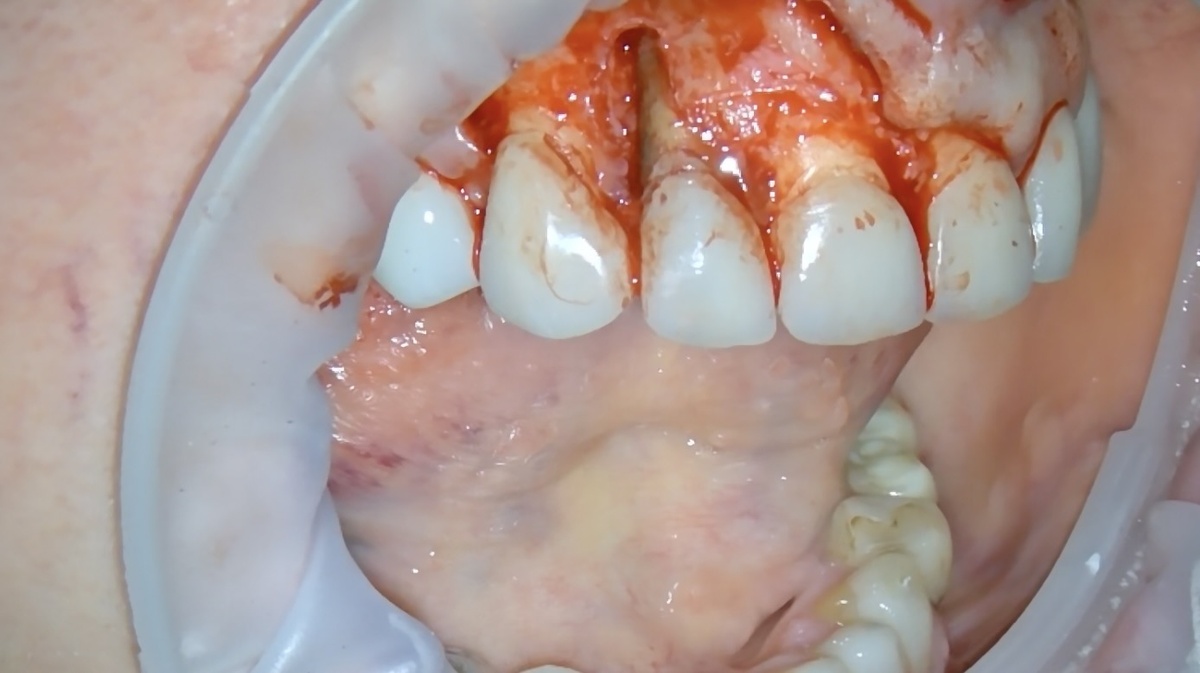

Хирург делает разрез. Откидывает лоскут.

И видит протяжённый костный дефект (фото с видео в микроскоп):

Костный дефект

Окрашивает ткани корня специальным синим красителем, который проявляет то, что невозможно разглядеть иначе. И вот тут - то самое, чего никто не ждал.

Продольные трещины корня.

Продольный перелом корня зуба

Всё, операция закончена.